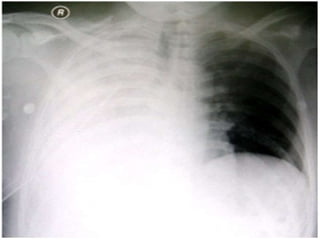

Imaging – Plain Films

• Choice of imaging modality depends on

nature of injuries and stability of patient.

• Knowledge of injury mechanism and index of

suspicion most important

• Can be performed at bedside

• Useful for rapid identification of

pneumothorax, hemothorax, fractures and

locating ballistics

Imaging – PlainFilms • Choice of imaging modality depends on nature of injuries and stability of patient. • Knowledge of injury mechanism and index of suspicion most important • Can be performed at bedside • Useful for rapid identification of pneumothorax, hemothorax, fractures and locating ballistics